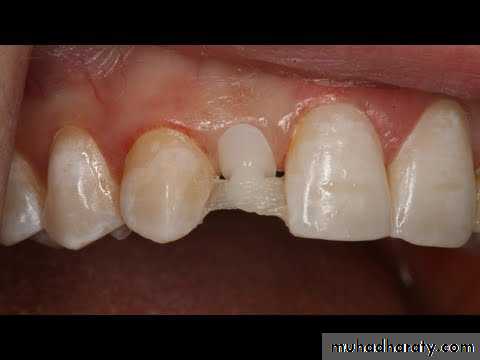

Traditional metal reinforced bridges are characterized by certain

• disadvantages. These disadvantages culminate in the bonding and aesthetic problems of metalframeworks. Fortunately, these problems can now be overcome,• to a large extent, by the use of fiber reinforced composite (FRC). In fact, the bond strength between the prostheses and the abutment teeth obtained when using FRCmaterials is 50-100 % higher than the bond strength achieved when using metal framworke

In addition, in FRC restorations the glass fibers are translucent and covered with veneering composites resulting in good aesthetic restorations, which do not increase plaque accumulation.

Metal-free prostheses continue to gain interest. Although the metalalloys contribute great strengthto the prostheses, they do so at

a considerable aesthetic liability. somewhat different metal -free approaches to fixed tooth replacement continue to be developed for a variety of clinical applications.